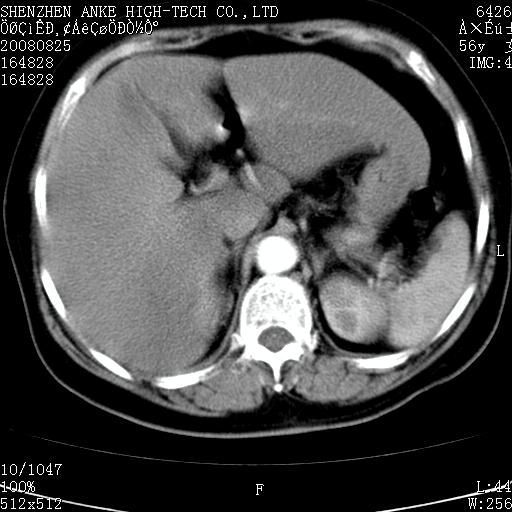

患者,女性,56岁,腰痛3年,查:右腹部约8x10cm肿块,固定,无压痛;8月23日在外院做了平扫,发现右肾巨大肿块(外院具体诊断不祥);今天在我院做了静脉肾盂造影,示:右肾明显增大,分泌功能明显减弱。

1)考虑右肾癌并右肾静脉瘤栓形成。2)脂肪肝。